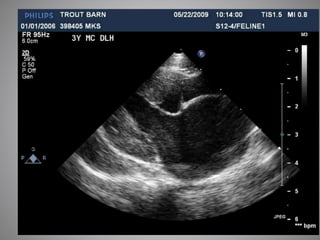

 Cats: Usually required

 HCM vs RCM vs UCM vs DCM vs DRVOTO

 Thrombus formation

 End stage disease